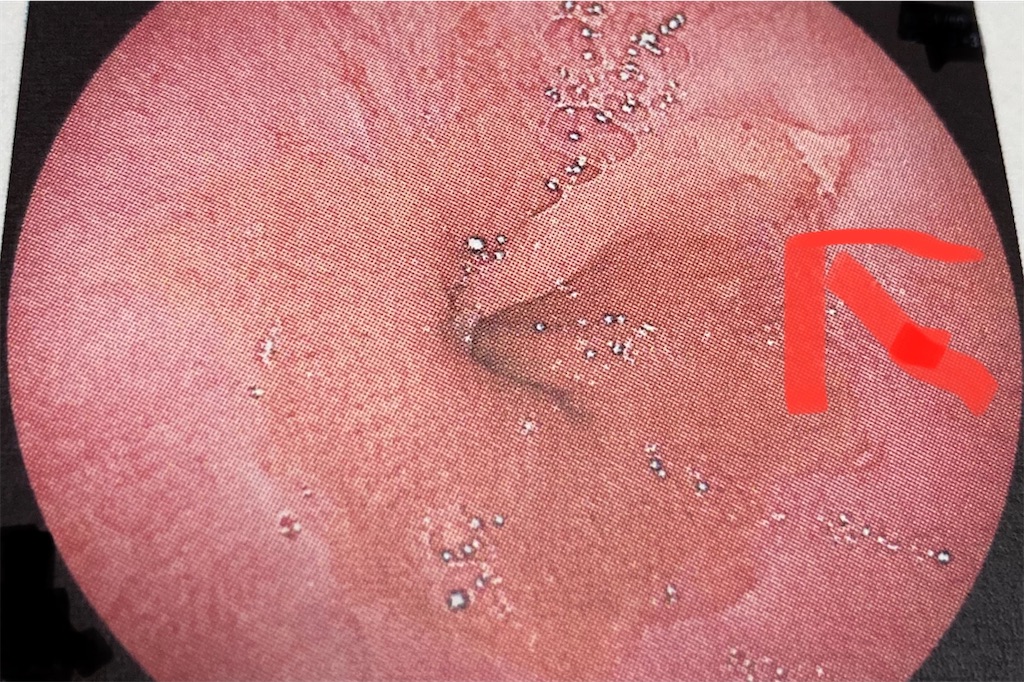

診察の結果、逆流性食道炎と言われた。

食道と胃の境目(噴門)あたりの食道部分が傷んでいるそうだ。

この食道の傷を常に目に入るところに貼っておいて、食道の傷を治すために食うことを抑えたいと思う。